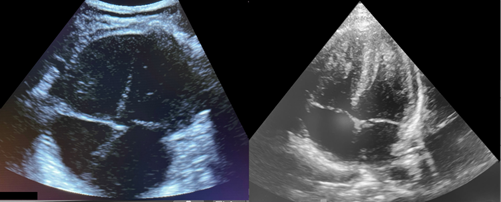

None of this has prevented the development of more distinct adaptations of POCUS for the pediatric population. Unique applications in children have included infant lumbar punctures guided by direct visualization of the cauda equina, protocols for intussusception, algorithms to confirm endotracheal tube placement, and the expansion of ultrasound first approach to appendicitis among many more yet at bedside. Bedside experience coupled with research has uncovered unique advantages our smaller patients offer in regard to image depth and clarity for structures not well imaged in adults. As a result, what has followed includes specific probe advancements allowing access to higher frequency and smaller footprints. This has allowed visualization of submillimeter neonatal vasculature and the ability to peer between infant ribs and tailor neonatal presets.

Figure 2. Comparison of an adult microconvex probe set to adult cardiac preset (L) and neonatal phased array probe set to neonatal Preset (R)